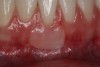

Once the flap was coronally repositioned and secured, a securing periosteal tac procedure was performed to prevent any micro movement superior to the mucogingival junction in the initial healing phase. A 4.0 chromic gut suture (Surgical Specialties Corp.) was used to engage the periosteum superior to the mucogingival junction and stabilize the tissues superior to the securing suture (Figure 12 and Figure 13). Multiple periosteal tac sutures may be necessary, depending on the size of the surgical field. Postoperatively, the periosteal tac sutures are routinely removed if not totally absorbed at 7 days; the flap sutures are removed at 2 to 3 weeks, and dermal-securing sutures are removed 1 month after surgery. The 1-year post-treatment clinical view shown in Figure 14 depicts the excellent soft-tissue result, band of attached keratinized tissue present, and excellent color match to the host gingival tissues.

Fig 14. One-year postoperative view of case presented.

Figure 14